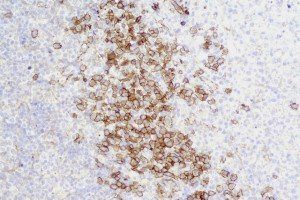

It is the ICU physician who is most likely to witness one of the deadliest manifestations of the abnormal immunological response, the cytokine storm syndrome (CSS). This response is also referred to by some as the cytokine release syndrome (CRS). CSS is characterized by continuous activation and expansion of macrophage and lymphocyte populations, which secrete large amounts of cytokines, causing the cytokine storm. This massive cytokine release is akin to hemophagocytic lymphohistiocytosis (HLH) disease, a syndrome characterized by initial unchecked and persistent activation of cytotoxic T lymphocytes and NK cells.

Clinical and laboratory manifestations of HLH include fever, enlarged liver and/or spleen, neurologic dysfunction, coagulopathy, liver dysfunction, cytopenias (i.e., low levels of erythrocytes, leukocytes, and/or platelets), hypertriglyceridemia, hyperferritinemia, hemophagocytosis, and eventually diminished NK cell activity as the immune system becomes progressively paralyzed. HLH can be familial (primary HLH) or secondary to another disease process (sHLH), such as rheumatic disease, in which it is referred to as macrophage activation syndrome (MAS, characterized by elevated ferritin).